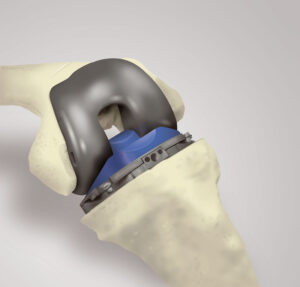

La cirugía de reemplazo articular de rodilla consiste en la eliminación del cartílago y huesos dañados de su rodilla, para posteriormente colocar una prótesis total/parcial de rodilla.

Al reemplazar una articulación dañada por una prótesis articular, el dolor desaparece o disminuye de forma considerable en la mayoría de los casos, mejorando su calidad de vida.